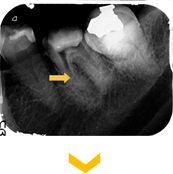

左下小臼歯の動揺を主訴に来院。根管内容物と最近感染組織を除去し、根管内を消毒し吸収した骨が回復となった。

歯根周囲に骨透過像が認められる。細菌感染により骨が吸収が疑われる。骨吸収により動揺が認められた。

歯根周囲に骨透過像が認められる。細菌感染により骨が吸収が疑われる。骨吸収により動揺が認められた。

根管治療後。歯根周囲に骨の回復を認める。歯の動揺も無くなり、被せ物をして、問題無く機能している。

根管治療後。歯根周囲に骨の回復を認める。歯の動揺も無くなり、被せ物をして、問題無く機能している。